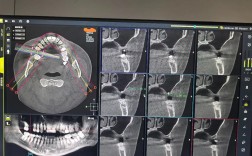

上牙植骨是口腔种植修复中常见的辅助手术,主要用于解决上颌骨骨量不足的问题,为种植体提供稳固的“地基”,其时间安排并非固定,而是受多种因素影响,涵盖术前准备、手术实施、骨愈合及最终修复等多个阶段,整体周期从数月到一年不等,以下从不同阶段详细解...

种植牙对上颌骨厚度有非常直接且重要的影响,可以说上颌骨的厚度(以及高度)是决定种植牙成功与否和手术方案的关键因素之一,以下是种植牙与上颌骨厚度关系的详细说明:上颌骨厚度的重要性种植体植入的基础:种植体需要植入到牙槽骨(上颌骨的一部分)中,...